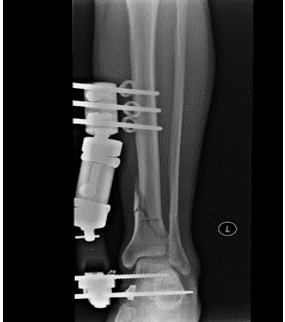

Monolateral external fixator

Name that technique